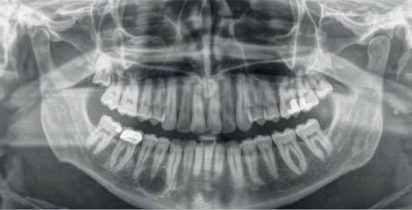

Solidny aparat RTG 2D dla gabinetów w większym stopniu zorientowanych na ekonomiczne rozwiązania. Urządzenie poziomu podstawowego, zapewniające bezproblemowy pierwszy krok do środowiska obrazowania cyfrowego dzięki niezawodnej diagnostyce zapewnianej przez technologię czujnika CsI i nieskomplikowanej obsłudze. Opcja ramienia cefalometrycznego powoduje, że Orthophos E jest również niezawodnym narzędziem w ortodoncji. Poszerz ofertę terapeutyczną swojego gabinetu o szeroki zakres usług dostępnych wyłącznie dzięki wykorzystaniu obrazowania cyfrowego.